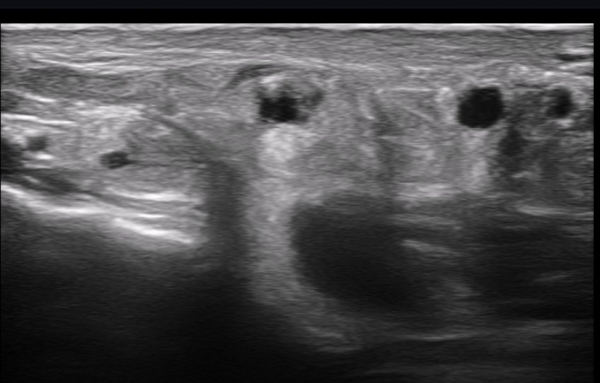

ÃÊÀ½ÆÄ ¼Ò°ß : ºñº¹½Å°æ Ⱦ´Ü¸é°Ë»ç¿¡¼­(»çÁø 1~13) ºñº¹½Å°æÀÇ Àú¿¡ÄÚ ºÎÁ¾°ú ´Üºñ°ñ°Ç³» ³¶Á¾¼º º´º¯ÀÌ °üÂûµÈ´Ù.

ºñº¹½Å°æ Á¾´Ü¸é°Ë»ç(»çÁø 14, 15)¿¡¼­ ºñº¹½Å°æÀÇ Àü¹ÝÀûÀÎ Àú¿¡ÄÚ ºÎÁ¾°ú ºñº¹½Å°æ ½ÉÃþÀ¸·Î ´Üºñ°ñ°Ç³»

³¶Á¾¼º º¯º¯ÀÌ °üÂûµÈ´Ù.